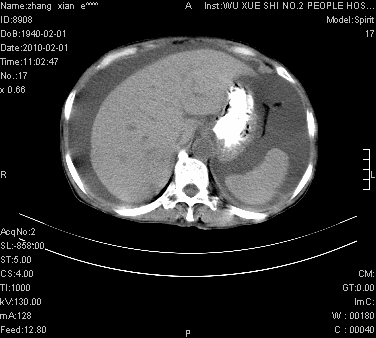

大量腹水,脾脏囊性占位,子宫颈占位,右侧腹股沟淋巴结肿大,建议+c,先查妇科。

腹盆腔大量积液,子宫增大,子宫颈增大外形不规则,内见低密度影,膀胱后壁显示不清,右腹股沟肿大淋巴结,脾脏囊性占位,子宫颈占位,子宫颈癌?建议增强。

腹盆腔大量积液,子宫增大,子宫颈增大外形不规则,内见低密度影,膀胱后壁显示不清,右腹股沟肿大淋巴结,脾脏囊性占位,子宫颈占位,子宫颈癌?建议增强。支持!

大量腹水,右肾、脾囊肿可能性大          考虑左侧附件区占位,建议增强